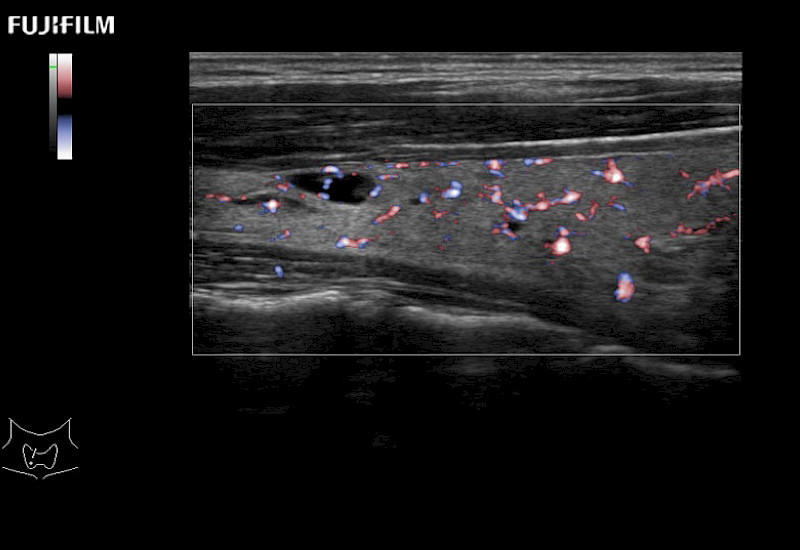

For precise surgical oncology ultrasound imaging, Fujifilm Healthcare offers premium level solutions that include:

Extraordinary high-resolution digital imaging

Multi-Parametric imaging modalities

Our dedication to Surgical Oncology allows us to offer superior image quality, outstanding system reliability and intuitive use of cutting edge technology.

The ARIETTA 750 incorporates all of the proven technologies and functions that medical professionals have come to expect from Fujifilm Healthcare.

ARIETTA 750 is the definitive diagnostic ultrasound solution for any clinical setting - Private Office, Imaging Center, or Hospital. The ARIETTA platform provides the ultimate in clinical performance with its state-of-the-art features and large user-friendly display.

The ARIETTA 650 DI combines trusted Fujifilm Healthcare technologies and features tailored for surgical oncology.

Designed to meet the demands of surgeons, the ARIETTA 650 DI offers precise guidance. Its advanced capabilities and large, intuitive display offer accurate and efficient care in operating rooms and specialized surgical settings.